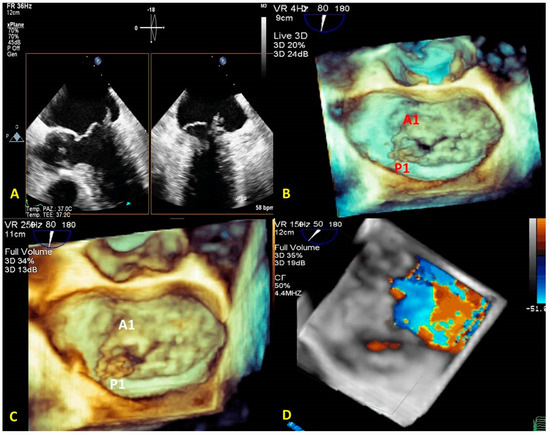

- Zoom mode: If zoom RT3DE is activated, two orthogonal 2D preview images show the ‘‘truncated’’ pyramid sector that the operator can move over the region of interest, regulating width and length and preventing respiratory or rhythm artifacts. However, it is limited by a low temporal resolution that can be improved by minimizing the sector’s width and length. (Figure 2B).

- “Full volume multiple beat” with or without color Doppler. This modality implies an electrocardiogram (ECG) synchronization permitting the analysis of an extensive volumetric data set by acquiring narrow subvolumes (two-seven sequential cardiac cycles). High spatial and temporal resolutions and a global MV view with excellent image quality represent the greatest strength of this modality (Figure 2C).

3.1. Anatomical Characterization